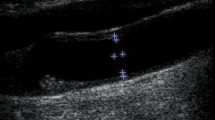

Clarifying the complex interaction between mechanical and biological processes in healthy and diseased conditions requires constitutive models for arterial walls. In this study, a mathematical model for the displacement of the carotid artery wall in the longitudinal direction is defined providing a satisfactory representation of the axial stress applied to the arterial wall. The proposed model was applied to the carotid artery wall motion estimated from ultrasound image sequences of 10 healthy adults, and the axial stress waveform exerted on the artery wall was extracted. Consecutive ultrasonic images (30 frames per second) of the common carotid artery of 10 healthy subjects (age 44 ± 4 year) were recorded and transferred to a personal computer. Longitudinal displacement and acceleration were extracted from ultrasonic image processing using a block-matching algorithm. Furthermore, images were examined using a maximum gradient algorithm and time rate changes of the internal diameter and intima-media thickness were extracted. Finally, axial stress was estimated using an appropriate constitutive equation for thin-walled tubes. Performance of the proposed model was evaluated using goodness of fit between approximated and measured longitudinal displacement statistics. Values of goodness-of-fit statistics indicated high quality of fit for all investigated subjects with the mean adjusted R-square (0.86 ± 0.08) and root mean squared error (0.08 ± 0.04 mm). According to the results of the present study, maximum and minimum axial stresses exerted on the arterial wall are 1.7 ± 0.6 and −1.5 ± 0.5 kPa, respectively. These results reveal the potential of this technique to provide a new method to assess arterial stress from ultrasound images, overcoming the limitations of the finite element and other simulation techniques.